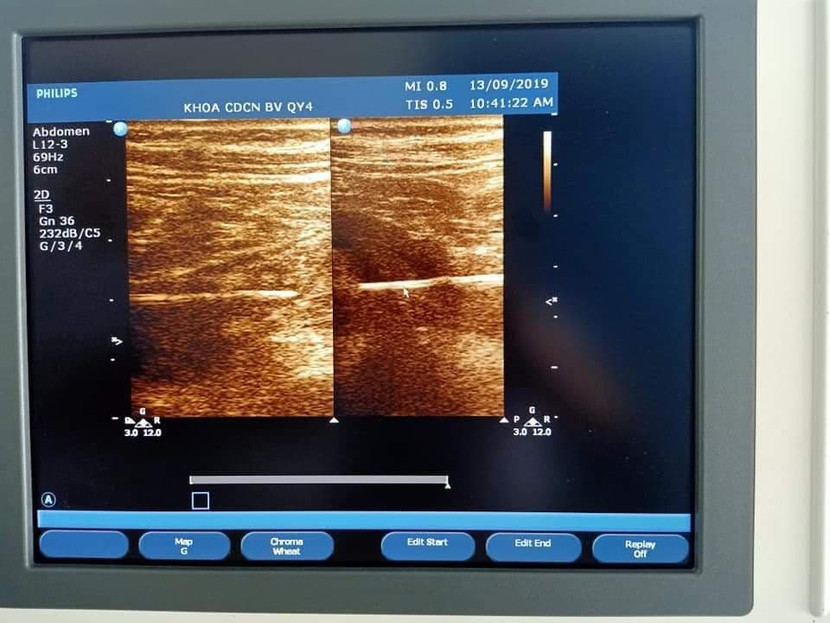

Hình ảnh siêu âm que tăm trong bụng nạn nhân

Qua siêu âm và chụp cắt lớp vi tính cho thấy hình ảnh chiếc tăm tre với một phần đầu nhọn đâm vào ruột non. Bệnh nhân được các bác sĩ nội soi, gắp que tăm dài 6 cm ra ngoài.